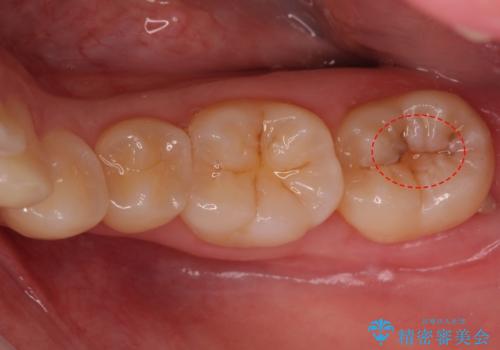

- 奥歯の樹脂の色が気になるとのことで来院されました。

変色しない材料での治療をご希望されたためセラミックインレーでの治療をしていくこととなりました。

継ぎ接ぎになった樹脂の詰め物から一塊のセラミックインレーに置き換えることで着色や二次う蝕のリスクを抑えます。